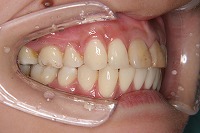

28歳6ヵ月

左